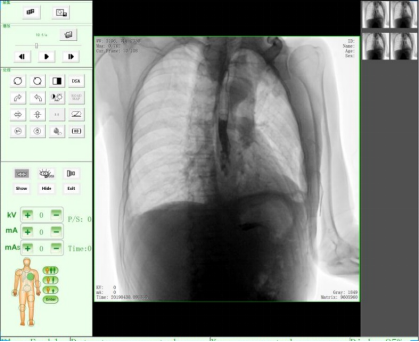

随着人们健康意识不断提高,越来越多人重视健康体检,而数字化DR拍片几乎是体检必检项目之一,胸片结果正常DR报告显示为:胸廓对称,两侧肋骨、肋间隙正常;两肺纹理清晰,未见明显实质性浸润;两侧肺门和纵隔影来见明显异常;心脏大小、形态在正常范围内;膈肌平滑,双侧肋膈角锐利时,则说明您一切正常。那么,数字化DR胸片报告不正常的结果有哪些呢?

2、密度不太高的、较为均匀的云絮片状影,边缘模糊,与正常肺间无清楚界限。

这就是在肺里该黑的地方变白了,它是由于急性炎症的渗出所致,当肺部急性炎症进展到某一阶段时,肺泡内气体即被由血管渗出的液体、蛋白及细胞所代替,形成渗出性实变。而这种实变取代了原先肺泡内的气体,从而挡住了X线,致使在数字化DR片上呈现出一片白色阴影。

3、两肺纹理增粗、紊乱,呈网状或条索状、斑点状阴影。

老慢支,肺气肿,肺心病,这时您的数字化DR片可能会呈现这种胸片,当进一步发展时,将会出现两肺透亮度增加。由于肺泡过度通气致使X光胸片上黑化度增加,即越黑透亮度越大。哮喘发作时同样可见两肺透亮度增加,呈过度充气状态。当然,X线摄影条件过高或是显影时间过长也会导致这样。

如果临床表现为在原有咳嗽、咳痰的基础上有逐渐加重的呼吸困难,甚至有胸闷、气急、桶状胸。常见的严重肺气肿、肺大泡还会导致气胸,也就是胸腔内的气体将肺压缩,使被压缩的肺与胸壁间出现透明的含气区,其中不见肺纹理。这些多是由白变黑的异常。